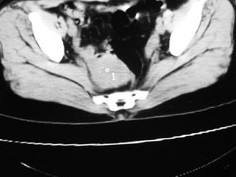

女42岁肛门下坠感4月余.

子宫轻度右倾,体后方见小似新月形低密度区,边界清楚。余所见无明显异常。

考虑:子宫直肠窝少量积液(盆腔炎所致)。